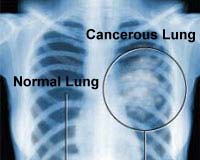

Lung Cancer Screening X Ray

Experience the clarity of Lung Cancer Screening X Ray with our curated collection of comprehensive galleries of images. featuring understated examples of photography, images, and pictures. designed to emphasize clarity and focus. Discover high-resolution Lung Cancer Screening X Ray images optimized for various applications. Suitable for various applications including web design, social media, personal projects, and digital content creation All Lung Cancer Screening X Ray images are available in high resolution with professional-grade quality, optimized for both digital and print applications, and include comprehensive metadata for easy organization and usage. Our Lung Cancer Screening X Ray gallery offers diverse visual resources to bring your ideas to life. Comprehensive tagging systems facilitate quick discovery of relevant Lung Cancer Screening X Ray content. Multiple resolution options ensure optimal performance across different platforms and applications. Time-saving browsing features help users locate ideal Lung Cancer Screening X Ray images quickly. The Lung Cancer Screening X Ray archive serves professionals, educators, and creatives across diverse industries. Instant download capabilities enable immediate access to chosen Lung Cancer Screening X Ray images. Whether for commercial projects or personal use, our Lung Cancer Screening X Ray collection delivers consistent excellence. Professional licensing options accommodate both commercial and educational usage requirements.